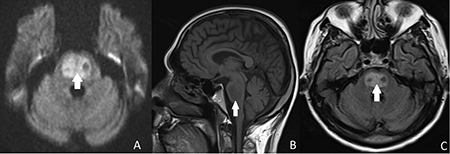

Brain magnetic resonance imaging of a patient with central pontine myelinolysis showing: (a) trident-shaped hyperintensity within the pons; (b) hypointensity within the basis pontis; and (c) hyperintense focus in the central pons

BMJ Case Reports 2013; doi:10.1136/bcr-2013-009970